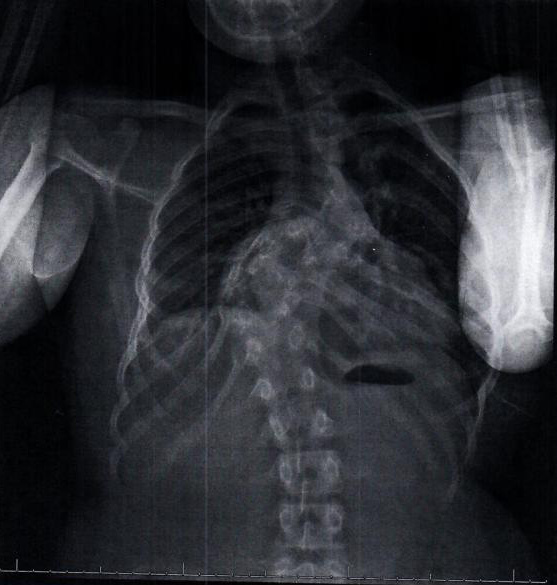

Hannah was born with congenital scoliosis and an “S” curve in her back. She has been followed by the Children’s Hospital of Philadelphia (CHOP) since she was one year old. As she has grown and developed, the curve in Hannah’s back has worsened, causing pressure on her lungs and in her chest cavity. As a natural athlete, this has been frustrating and scary for her. Her recent x-ray has shown that the curve in her back has shifted to 90 degree angle. This coupled with the other issues she is experiencing, the experts have decided that it is time for surgical intervention.